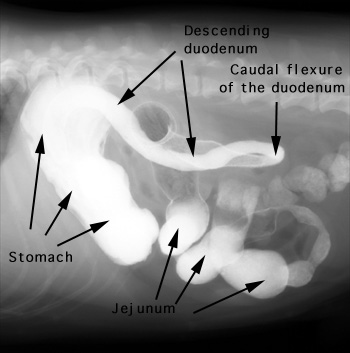

Barium was administered orally and the radiographs were taken 20 minutes later